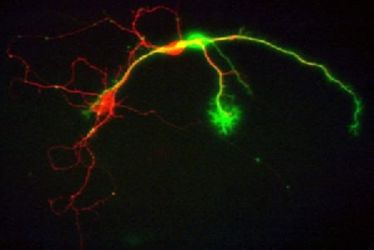

Neuroscience Colloquium Münster

Neuroscience Colloquium Münster

Neuroscience Colloquium Münster

Neuroscience Colloquium Münster

Neuroscience-Colloquium Münster

Neuroscience-Colloquium Münster

Neuroscience Colloquium Münster

Neuroscience Colloquium Münster

Neuroscience Colloquium Münster

Neuroscience Colloquium Münster

Neuroscience Colloquium Münster

Neuroscience Colloquium Münster

Neuroscience Colloquium Münster

Neuroscience Colloquium Münster

Neuroscience Colloquium

Neuroscience Colloquium